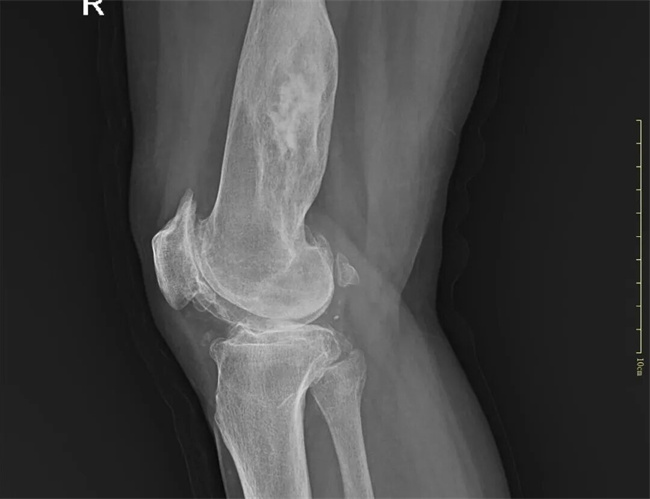

二、患者郭某某,女,59岁,患者行走跛行,右膝髌骨周围压疼明显活动受限20天余。为求进一步治疗,来到我院请专家会诊,通过各位专家会诊查体、查看影像资料并细致认真的分析后,诊断为:1.右膝关节骨性关节炎2.右股骨下段内生软骨瘤病。建议:住院保守治疗。